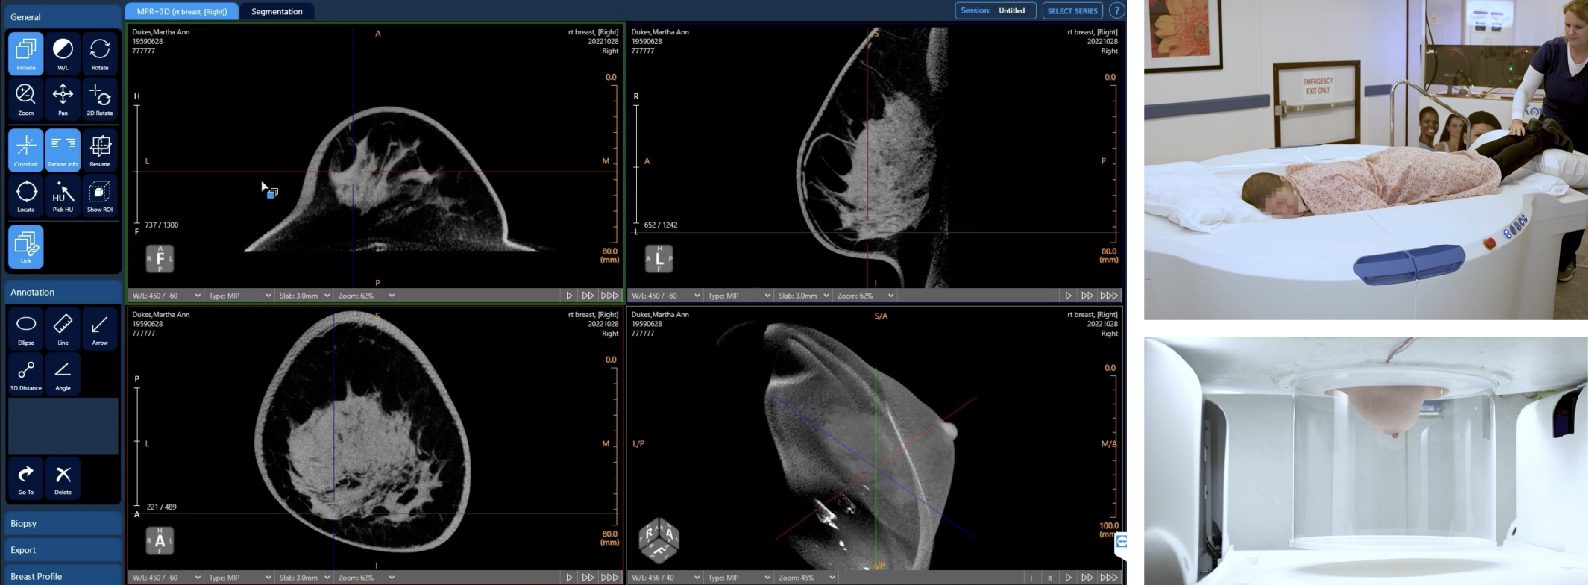

The Vera Scan offers a revolutionary approach to breast imaging by creating an exceptionally detailed view of the entire breast.

Unlike traditional mammography, which only captures a limited 15 to 50-degree portion of the breast, the Vera Scan rotates around the breast, delivering a complete 360-degree view. This advanced imaging technology provides a more comprehensive and detailed picture, improving diagnostic accuracy.

How Koning Vera Scan Works

During your appointment, you’ll lie on the machine while it takes a series of detailed 3D images.

Position: The imaging table is open with a depression in the center where the scanning takes place. The images are taken with you lying down so that the breast falls away from the body naturally.

Scanning Process: The CT scanner acquires high-resolution images of your breast from multiple angles without any direct contact on your body. The machine is quiet, without any significant sounds or vibrations of note.